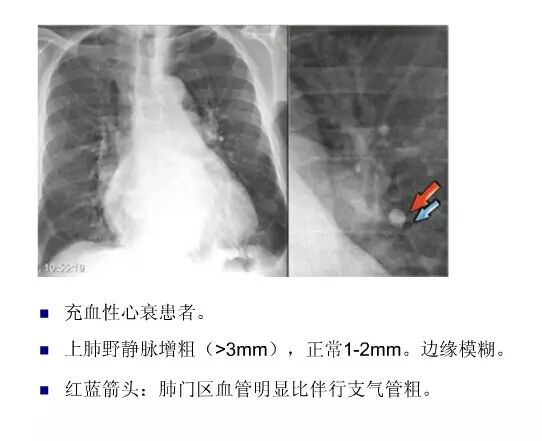

平片如何看心衰